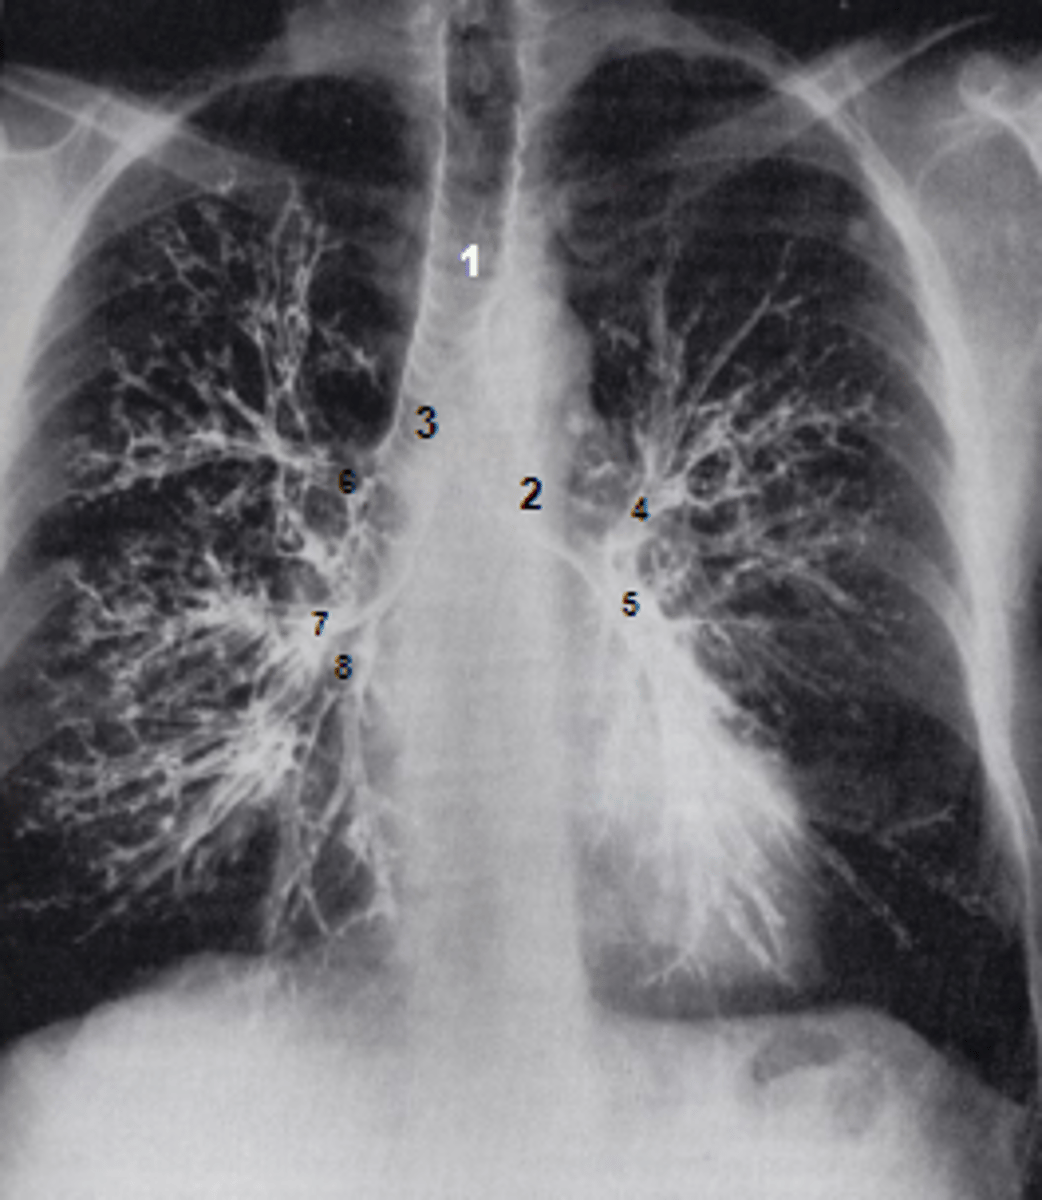

1

at what number is the trachea

2

at what number is the left main bronchus

3

at what number is the right main bronchus

4

at what number is the left superior lobar bronchus

5

at what number is the left inferior lobar bronchus

6

at what number is the right superior lobar bronchus

7

at what number is the right middle lobar bronchus

8

at what number is the right inferior lobar bronchus